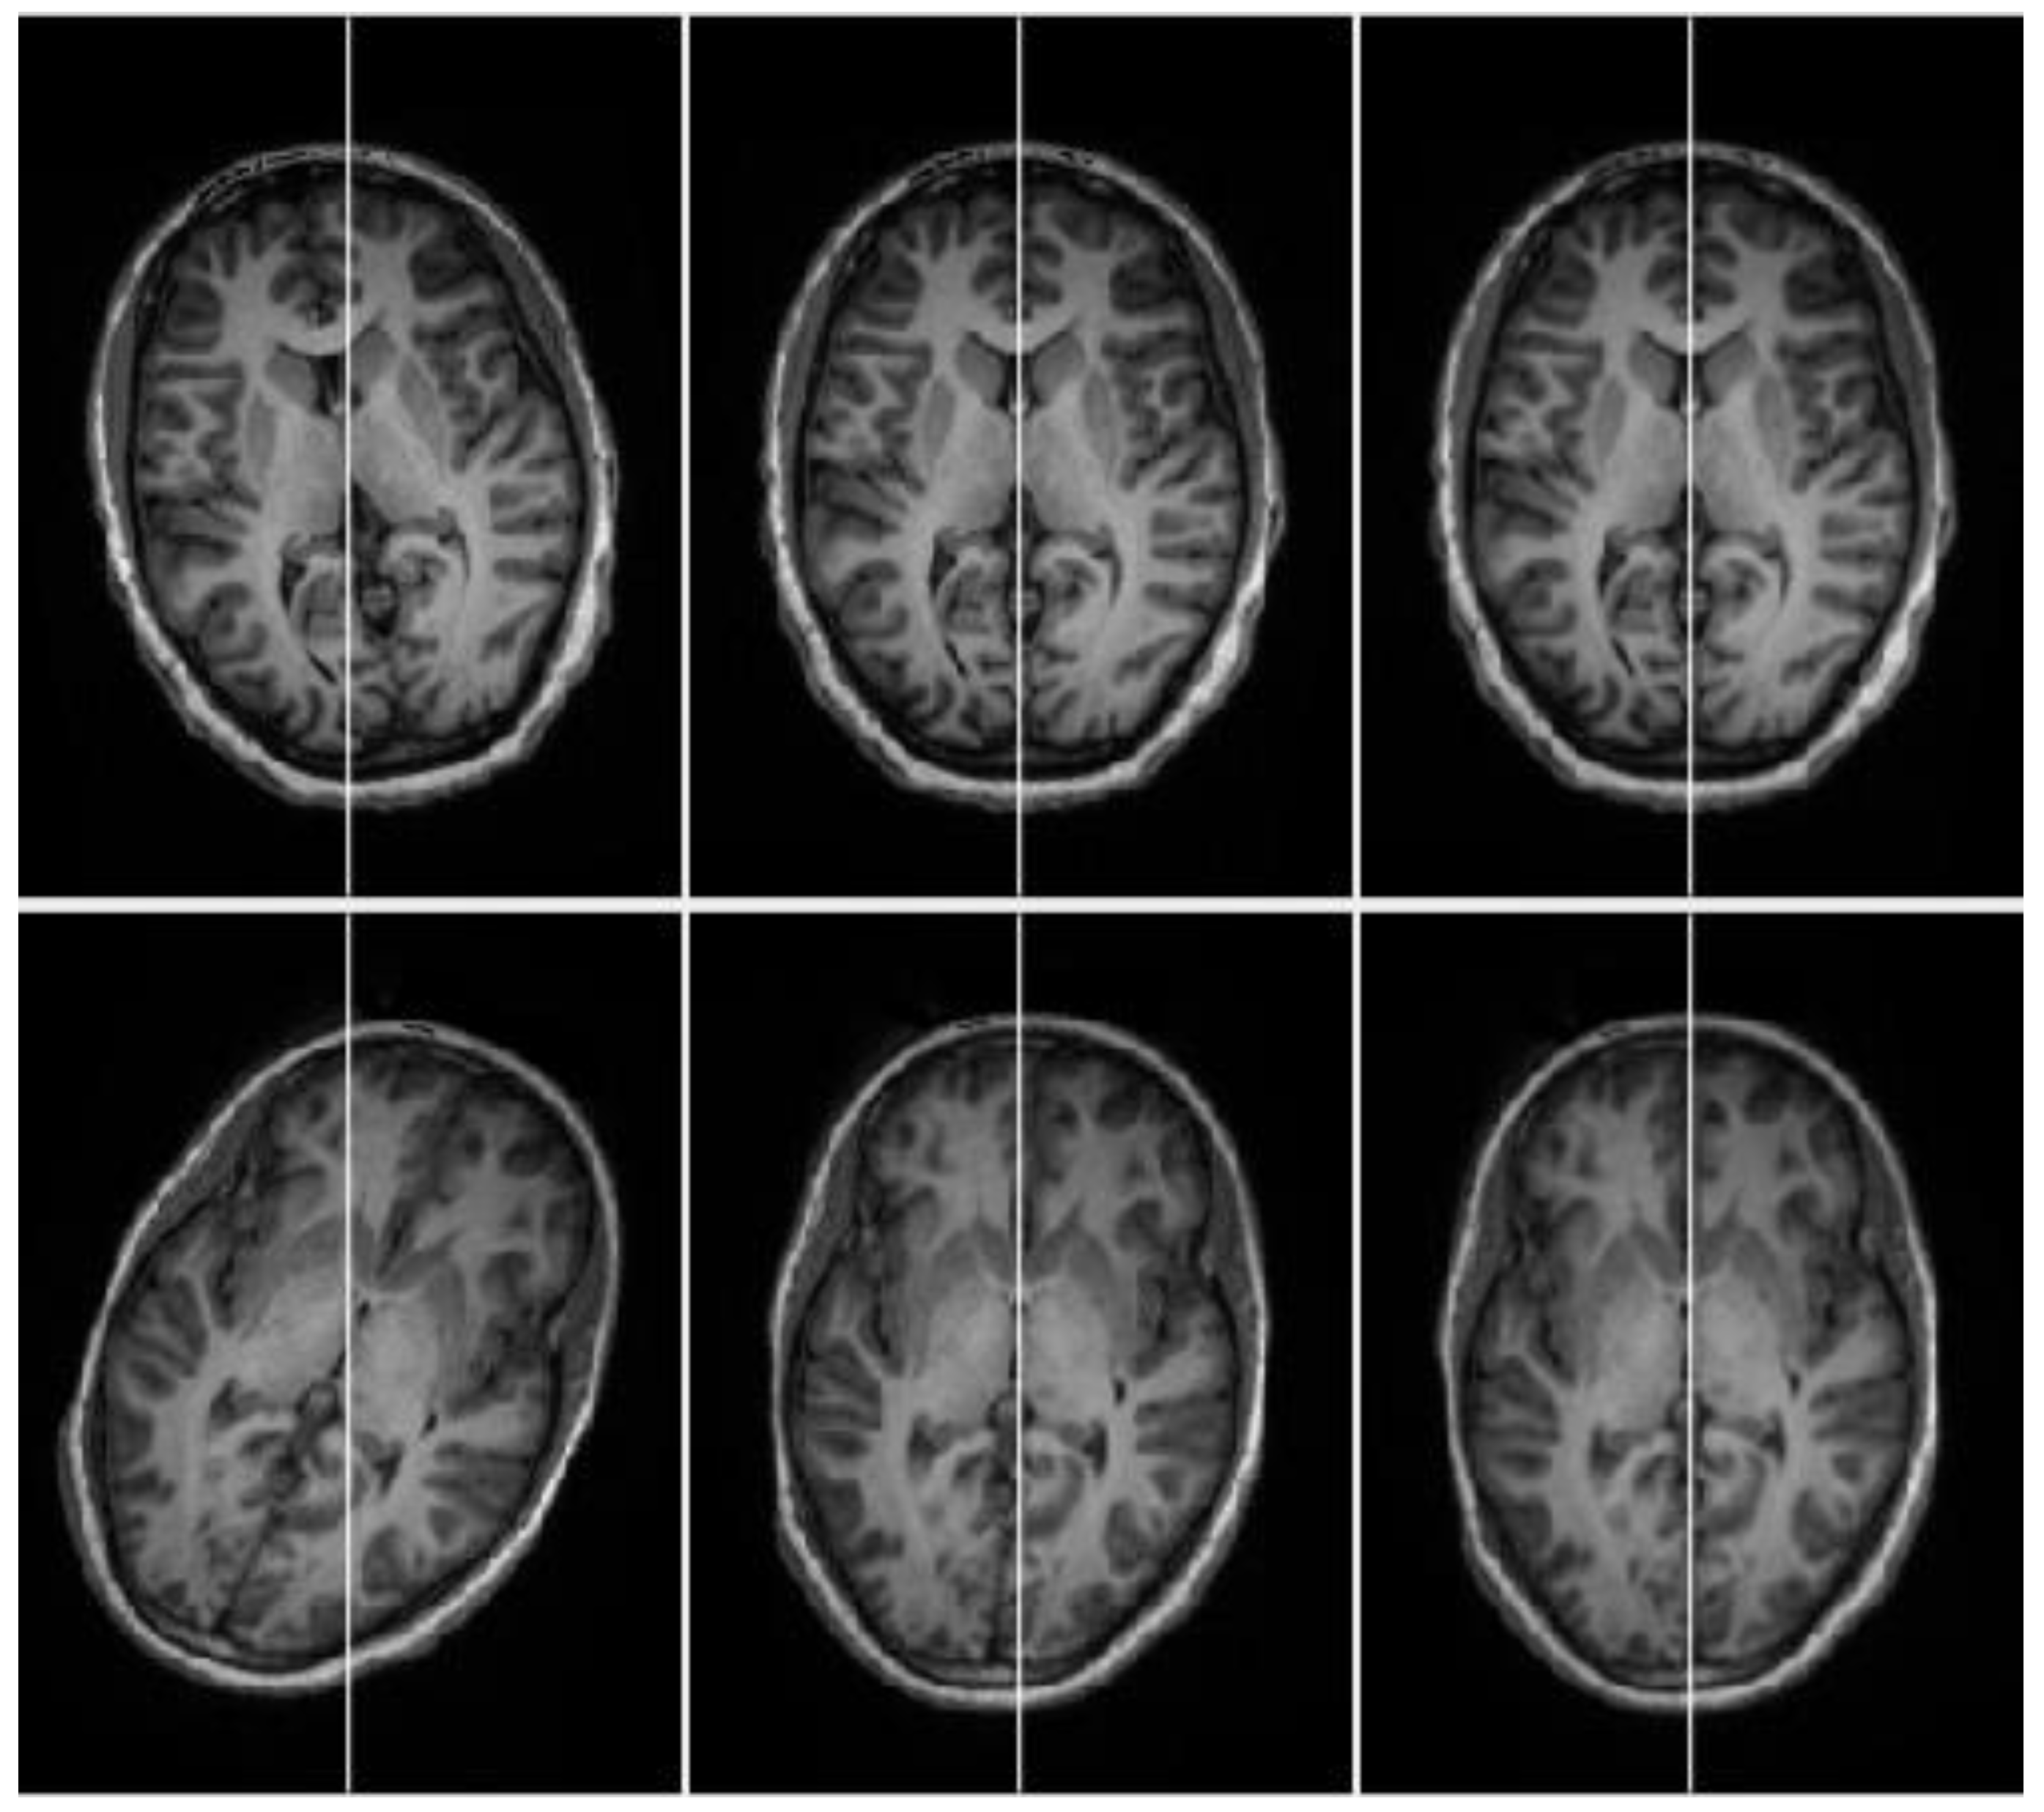

2.2.3. Cross-Correlation